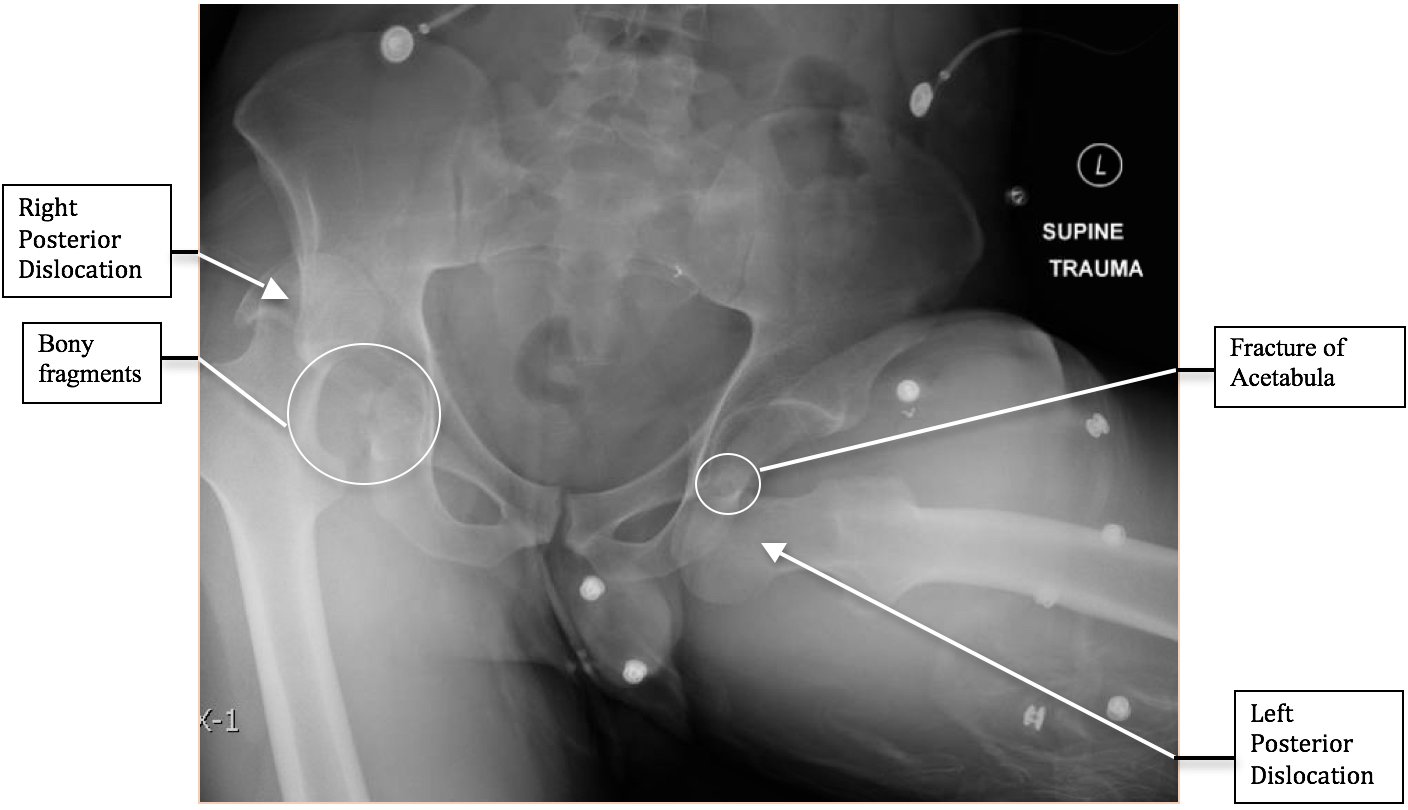

The initial radiograph of the pelvis revealed bilateral hip dislocations. Small bony fragments were noted in the right hip joint, suggestive of an underlying fracture. The sacroiliac joints and the pelvic ring were intact. In the emergency department, bilateral hip reductions were performed using the Captain Morgan technique.1 The post-reduction film showed reduction of the bilateral hip dislocations with extensive comminuted and displaced fractures of the right and left acetabula.